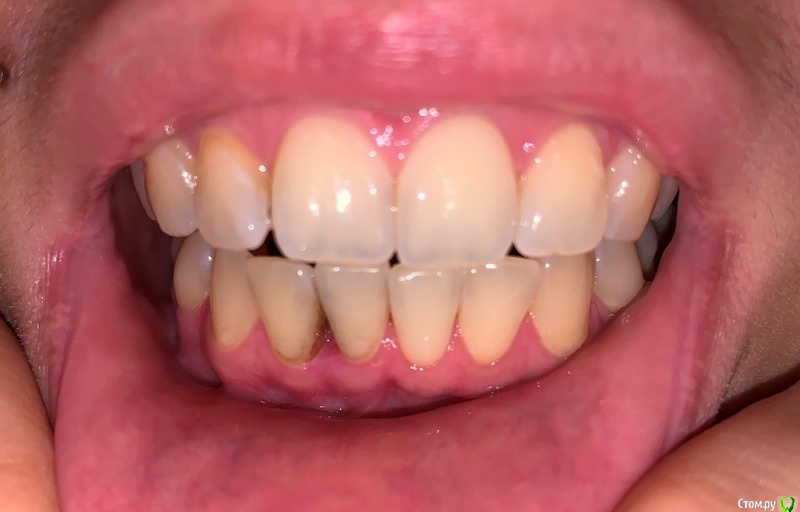

dentikl Опубликовано 9 января, 2021 Поделиться Опубликовано 9 января, 2021 нет, и не ела уже давнопокажите фото передних зубов Ссылка на комментарий

Diana1974 Опубликовано 9 января, 2021 Автор Поделиться Опубликовано 9 января, 2021 покажите фото передних зубовТакой нездоровый вид (цвет эмали между зубов и как будто бы рецессия) десна приобрела после посещения парадонтолога в начале декабря, врач предположил, что боль вызывает глубокий зубной камень под десной и сделал чистку ультразвуком, на ситуацию с болью в десне это никак не повлияло. Ссылка на комментарий